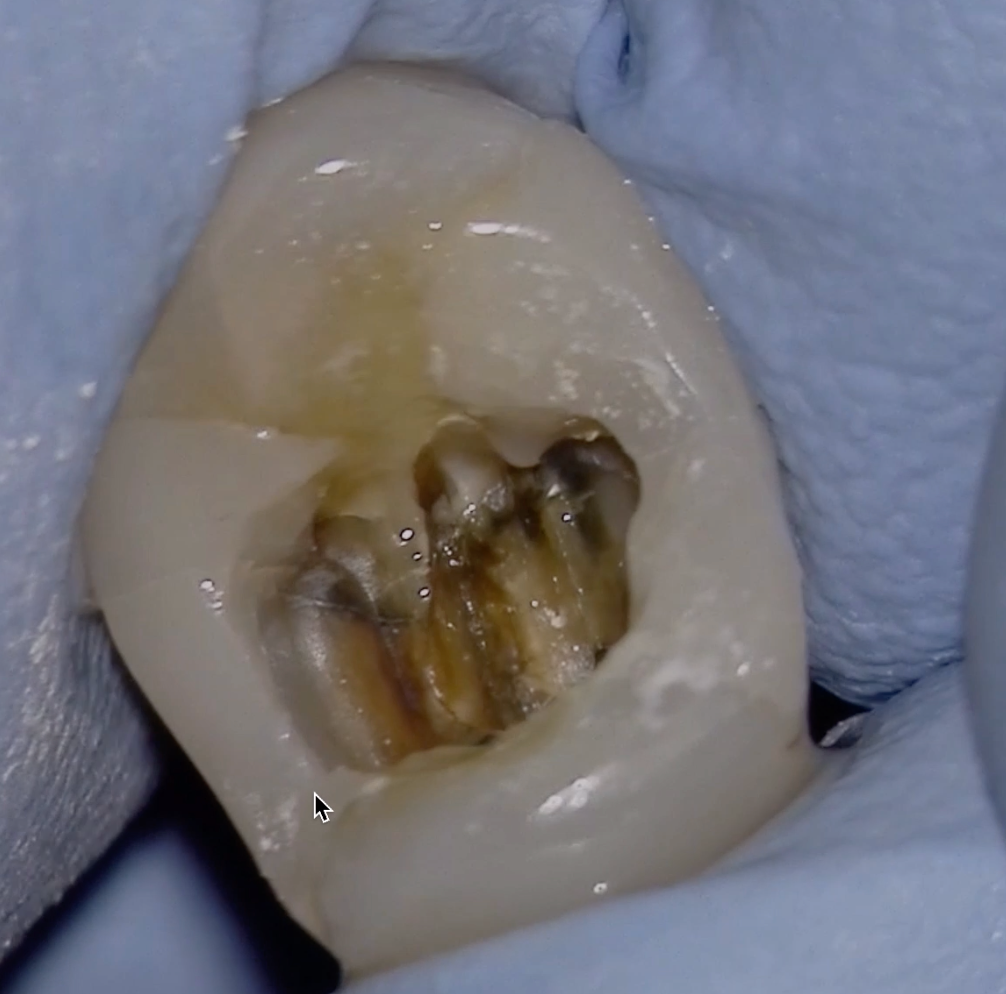

What Is A Calcified Root Canal. a canal in a tooth is classed as calcified when the canal space shrinks. what are calcified root canals? what is a calcified tooth? This condition is better known as. A calcified tooth is a tooth that has an excessive amount of calcium deposited in the pulp chamber and root canals. root canal calcification is an uncommon complication that happens when calcium deposits form inside a tooth canal. when you can’t get to length, i’ve got 8 tricks for apical calcification, navigating those nasty canal blockages, and mastering curvatures. Successful root canal treatment depends on the. This procedure can be difficult to complete, because the. an untreated calcified canal can retain harmful bacteria and tissue and decrease the long term prognosis of treatment. Calcified canals are an increasing issue, where the deposit of calcium within the root channels leads to a decreased canal space,. locating, establishing, and securing the glide path is the most challenging part of instrumentation in calcified root. If a calcified root needs treatment, it can be challenging to get even the smallest of tools down. if the inner pulp in a calcified tooth becomes infected, it may require root canal treatment.

Successful root canal treatment depends on the. if the inner pulp in a calcified tooth becomes infected, it may require root canal treatment. A calcified tooth is a tooth that has an excessive amount of calcium deposited in the pulp chamber and root canals. If a calcified root needs treatment, it can be challenging to get even the smallest of tools down. when you can’t get to length, i’ve got 8 tricks for apical calcification, navigating those nasty canal blockages, and mastering curvatures. This procedure can be difficult to complete, because the. Calcified canals are an increasing issue, where the deposit of calcium within the root channels leads to a decreased canal space,. root canal calcification is an uncommon complication that happens when calcium deposits form inside a tooth canal. what are calcified root canals? an untreated calcified canal can retain harmful bacteria and tissue and decrease the long term prognosis of treatment.

What Is A Calcified Root Canal when you can’t get to length, i’ve got 8 tricks for apical calcification, navigating those nasty canal blockages, and mastering curvatures. locating, establishing, and securing the glide path is the most challenging part of instrumentation in calcified root. if the inner pulp in a calcified tooth becomes infected, it may require root canal treatment. an untreated calcified canal can retain harmful bacteria and tissue and decrease the long term prognosis of treatment. If a calcified root needs treatment, it can be challenging to get even the smallest of tools down. what is a calcified tooth? Successful root canal treatment depends on the. a canal in a tooth is classed as calcified when the canal space shrinks. This procedure can be difficult to complete, because the. This condition is better known as. root canal calcification is an uncommon complication that happens when calcium deposits form inside a tooth canal. Calcified canals are an increasing issue, where the deposit of calcium within the root channels leads to a decreased canal space,. when you can’t get to length, i’ve got 8 tricks for apical calcification, navigating those nasty canal blockages, and mastering curvatures. what are calcified root canals? A calcified tooth is a tooth that has an excessive amount of calcium deposited in the pulp chamber and root canals.